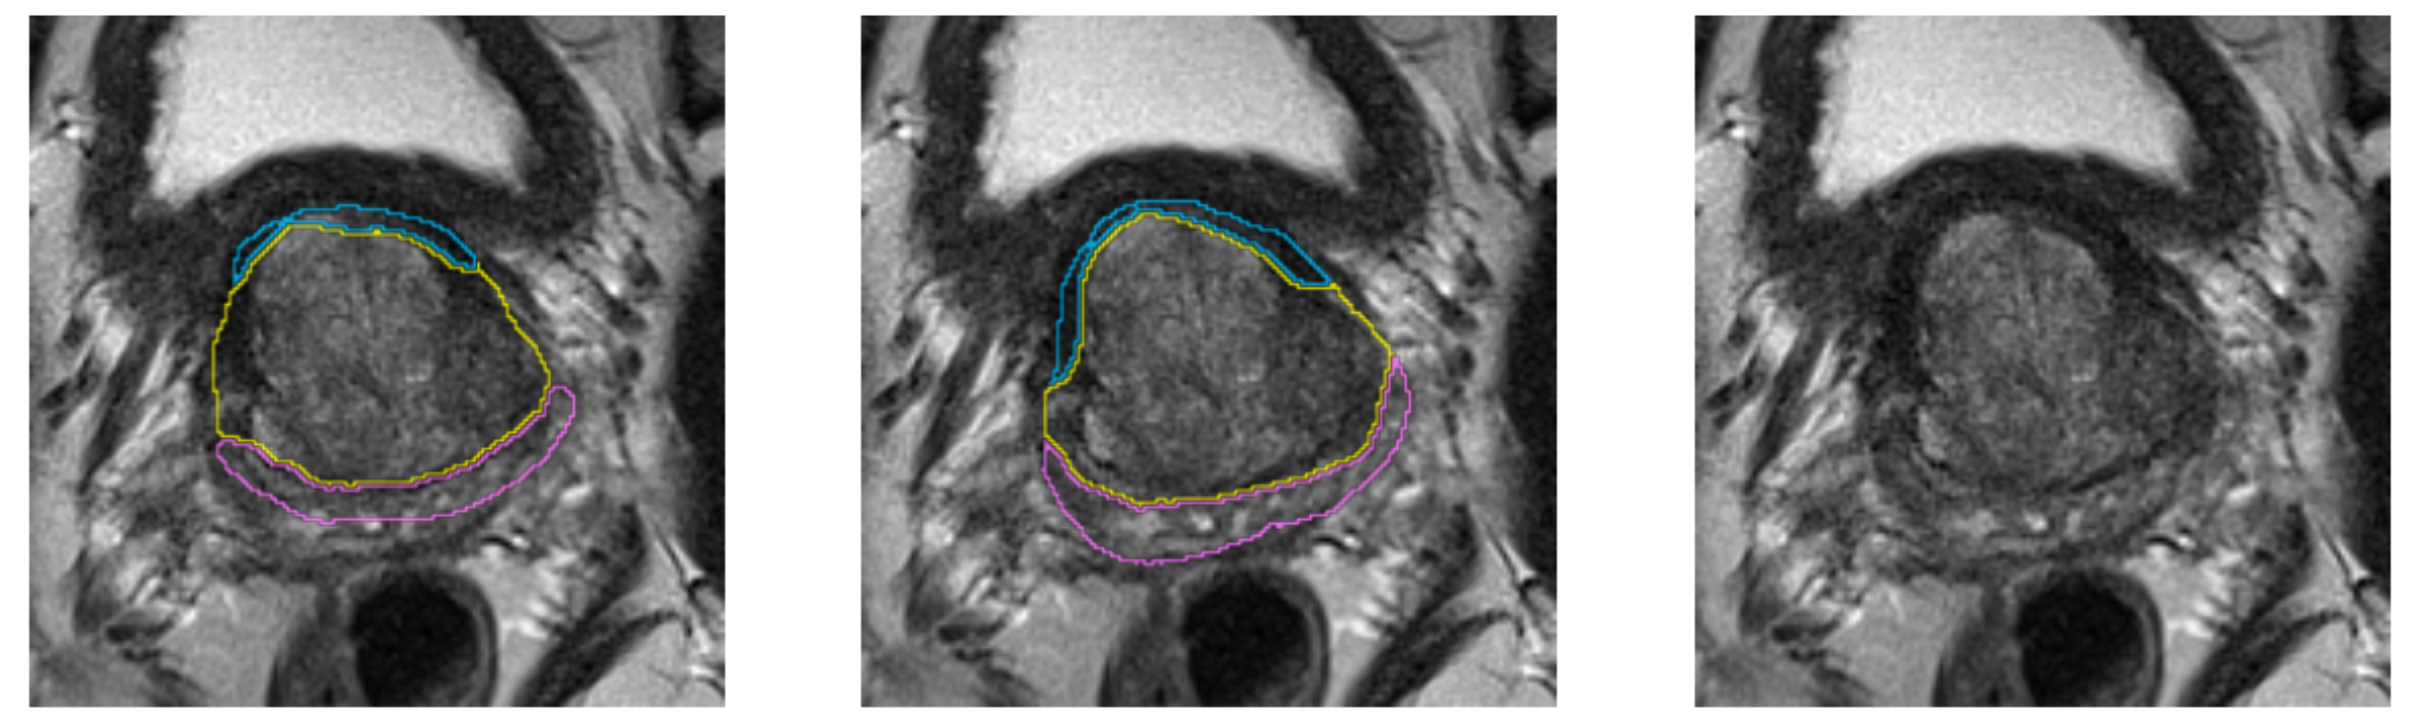

Multi-Label segmentation of anatomic prostate zones in MRI

The goal of this project is to evaluate and extend variants of a volumetric CNN for multi-label segmentation of prostate zones in MR images. The prostate zones are essential for lesion classification and therapy planning. After successful segmentation, a sector map could be extracted that is used for PI-RADS reporting. This has the potential to automate and better standardize prostate lesion location reporting. This project is a continuation of the project that we started in last Winter Project Week. We already have results, but especially in one zone, the algorithm does not work very well and is not stable.

Illustrations